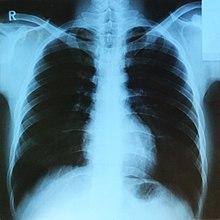

DICOM(Digital Imaging and Communications in Medicine)은 표준 의료영상/기록 포맷이다:

Figure 1.22 X-ray 영상 - 의료 영상의 기본적인 형태